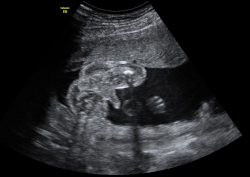

Ecografía semana 20: Vídeo del aparato genital de un niño

En esta ecografía en 4D se distingue el escroto de este feto varón. En la ecografía de la 20 semanas de embarazo, es muy probable que la embarazada ya sepa el sexo de su bebé, ya que se puede ver en la semana 12. No obstante, ahora se confirma.

Ultrasonido del aparato genital masculino en tres dimensiones

Las imágenes dan buena cuenta del sexo del bebé: se aprecia la pierna, el escroto, el pie y el cordón umbilical de la criatura.